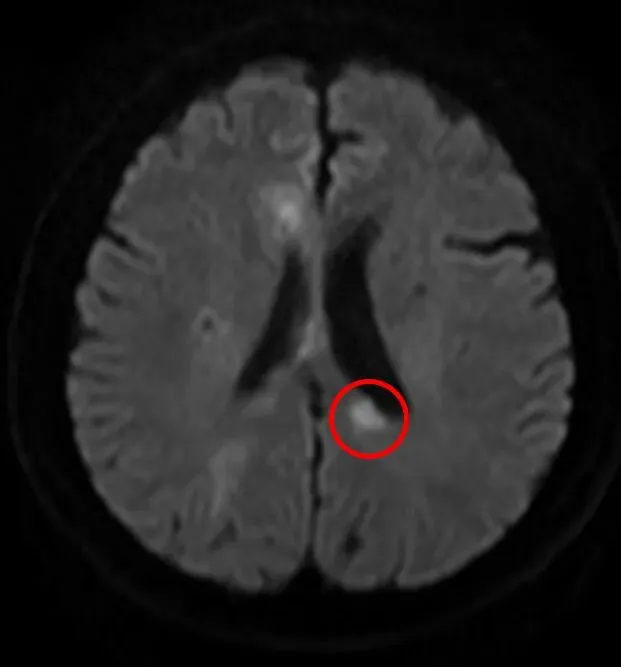

据了解,58岁的男性患者因“双膝关节麻木”入院,初诊时疑似腰椎相关问题。然而次日,患者出现感觉异常症状,经磁共振(MRI)检查确诊为双侧额顶叶多发新鲜脑梗死。医疗团队随即启动抗血小板、强化降脂等常规治疗,患者症状初步好转,但仅3天后病情便再次发作,复查MRI显示新增多处新发脑梗死,症状较前更为明显,常规治疗方案陷入瓶颈。

患者再次就诊,出现了新的脑梗死病灶